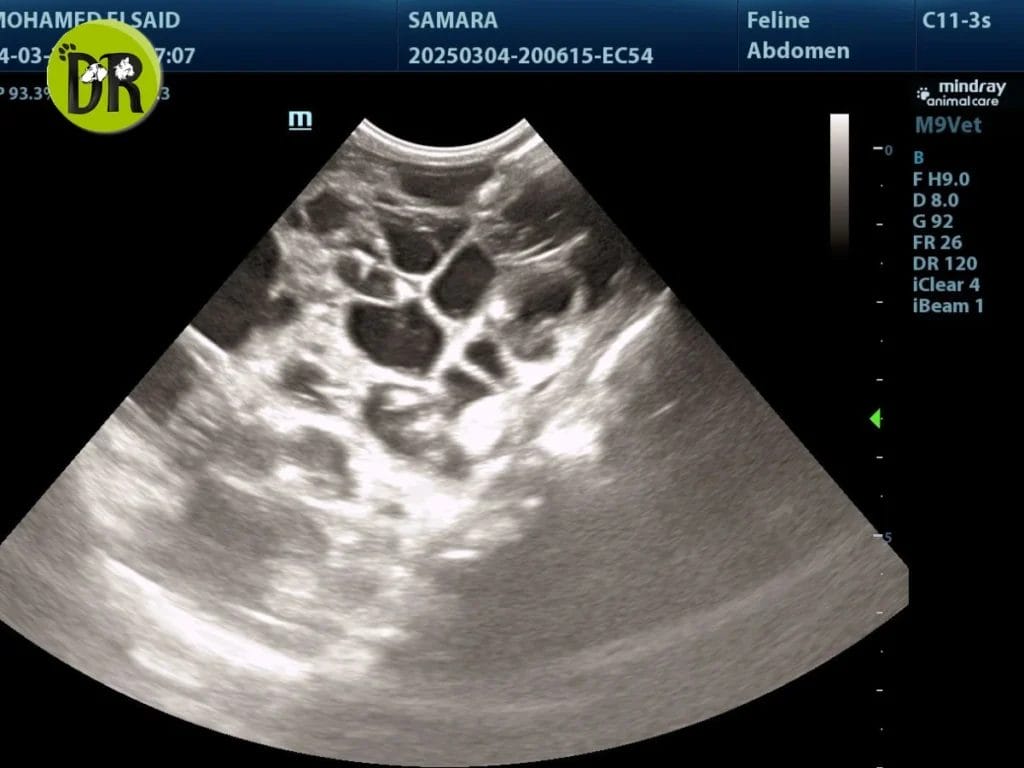

قصتنا اليوم عن سامارا، قطة شيرازي جميلة عمرها 3 سنوات، أُحضرت إلى عيادتنا بعد أن لاحظ أصحابها أنها أصبحت خاملة، لا تأكل مثل السابق، تفقد وزنها تدريجيًا، وتعاني من قيء متكرر مع شرب مياه وتبول بكميات أكبر من الطبيعي.

الفحص والنتائج

أثناء الكشف، قامت Dr. Nadia Essam بفحص سامارا ولاحظت رائحة أمونيا من فمها مع ألم واضح عند لمس الكليتين. وبعد إجراء الفحوصات المخبرية ظهر ارتفاع في مؤشرات وظائف الكلى.

ثم أجرى Prof. Mohamed El-Sayed فحص الموجات فوق الصوتية، والذي أظهر وجود أكياس داخل الكليتين، مؤكِّدًا إصابة سامارا بمرض PKD.

خطة العلاج

رغم أن المرض مزمن ولا يمكن عكسه، إلا أن العلاج يهدف إلى إبطاء تطوره وتحسين جودة حياة القط. اعتمد الفريق على:

- محاليل خاصة لتقليل السموم في الدم

- نظام غذائي منخفض البروتين مخصص لحالات الكلى

- أدوية للمساعدة في السيطرة على الفوسفور ودعم الكلى

كلمة من الفريق

بفضل متابعة Dr. Nadia Essam ووضع خطة علاج دقيقة، بدأت سامارا تستعيد نشاطها تدريجيًا، وتحسنت شهيتها، مما أعاد الطمأنينة لأسرتها التي كانت قلقة عليها بشدة.

هذه القصة تذكرنا بأهمية الفحص المبكر، خصوصًا للقطط الشيرازي والفارسية، حيث يمكن أن يكشف السونار الروتيني عن المرض قبل أن تتطور أعراضه الخطيرة.